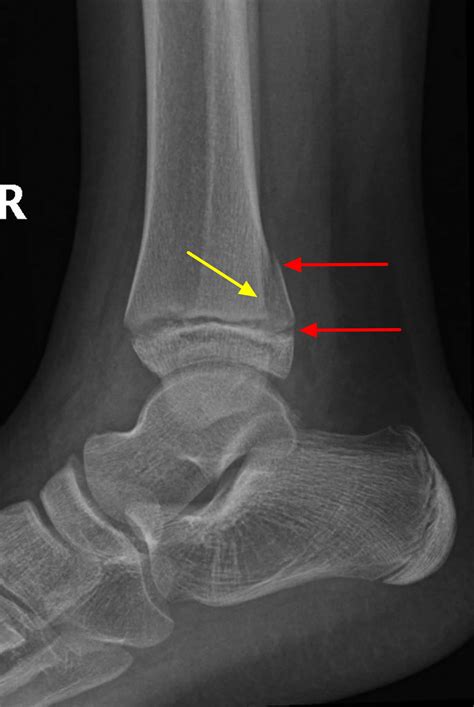

Diagnosing issues related to foot growth plates typically involves a combination of physical examination, imaging studies, and medical history. Common diagnostic tools include X-rays, MRI scans, and CT scans, which can provide detailed images of the growth plates and surrounding tissues. Treatment options vary depending on the severity and type of injury but may include: